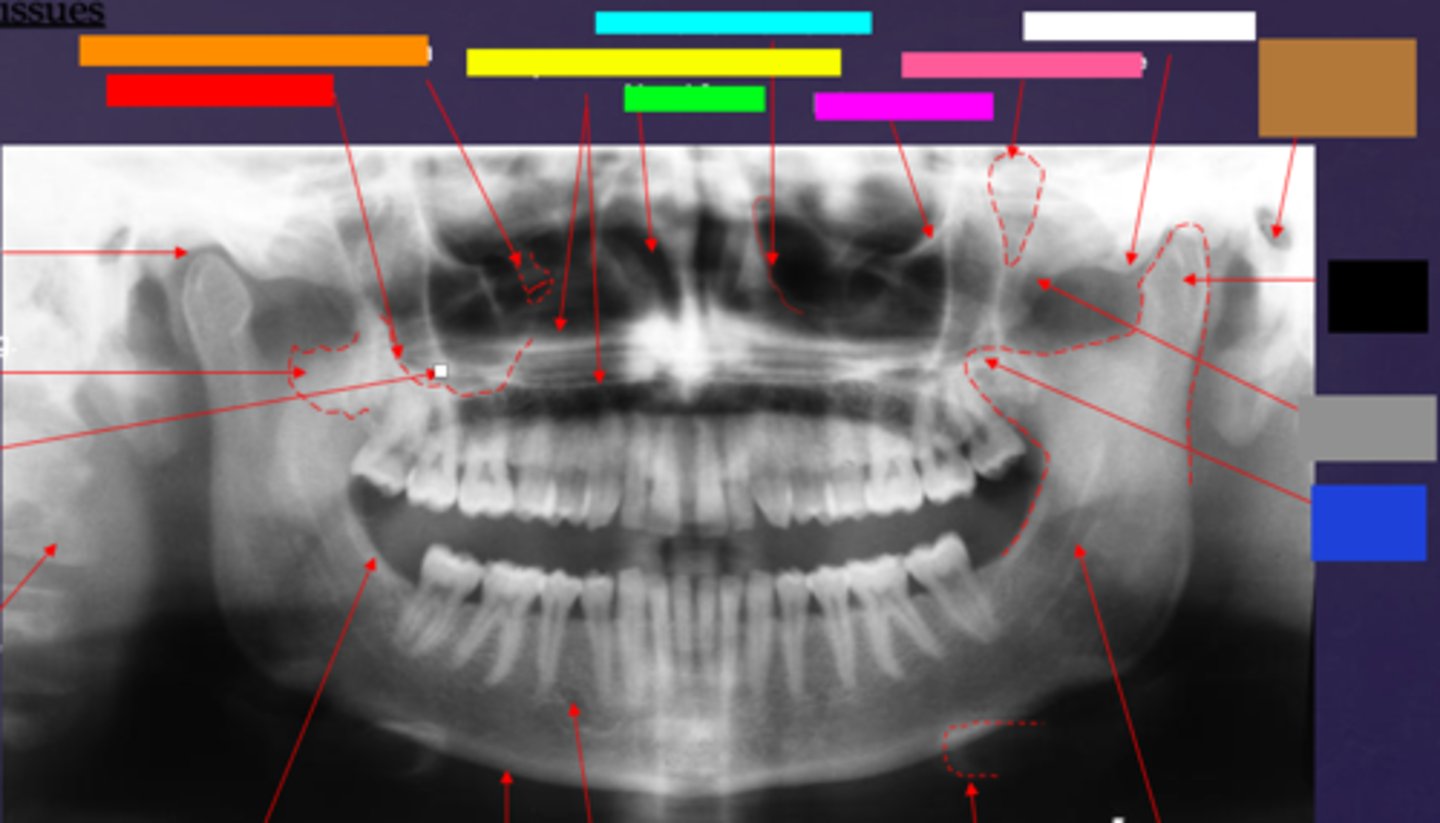

ID the soft tissue anatomy indicated by the arrow pointing from the red box:

ala of nose

ID the soft tissue anatomy indicated by the arrow pointing from the orange box:

nasal septum

ID the soft tissue anatomy indicated by the arrow pointing from the yellow box:

columna (the septum separating the nostrils)

ID the soft tissue anatomy indicated by the arrow pointing from the green box:

tragus

ID the soft tissue anatomy indicated by the arrow pointing from the light blue box:

ear lobe